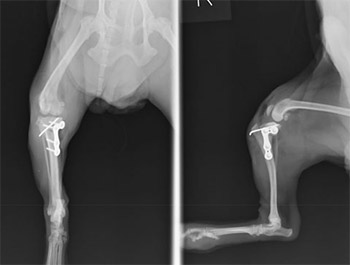

- まず半円形に骨を切断できる特殊なブレードを使用して脛骨の骨きりを行います。

- L字型の特殊プレートを使用して、角度を補正して骨きりした部分の固定を行います。

- 最後に膝蓋骨内方脱臼整復手術を同時に行い、手術終了としました。

-

術後レントゲンです。体重のかかる脛骨高平角が水平に近づきました。これなら体重をかけても痛みはほとんどでないと判断されます。

術後は2日目から負重可能となり、4日目からは歩行可能となりました。術後2週目には走れるようになり、その後の経過は良好でした。